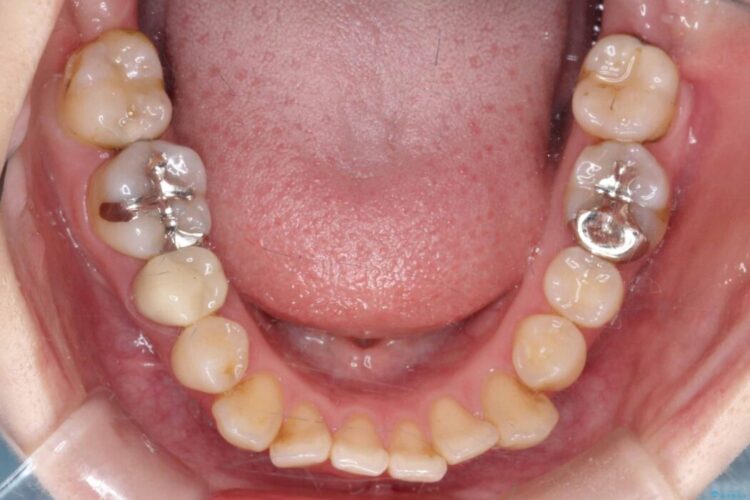

開咬、叢生、八重歯が気になるとご来院された患者様です。

精密検査の結果、上顎左右4番および下顎左右5番の計4本を抜歯し、目立ちにくいクリア装置にて治療を行いました。

また、虫歯があったので、矯正開始前に虫歯治療を行っております。